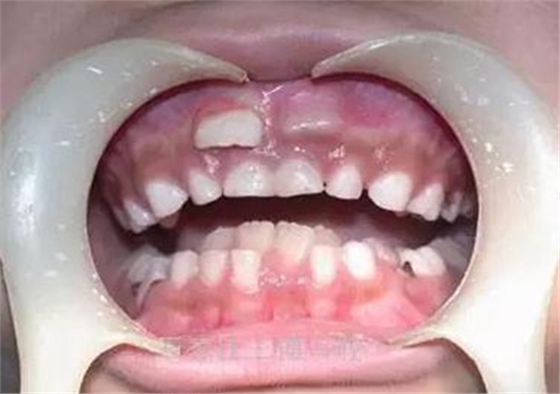

“為什么我會(huì)像鯊魚(yú)一樣有好多牙齒?”6歲的糖糖正值換牙期,想不到乳牙還沒(méi)脫落,就有兩顆恒牙在乳牙后面擠出來(lái)了,這讓糖糖看起來(lái)就像是有兩層牙齒的“小怪物”。原來(lái),乳牙未退同時(shí)恒牙生出造成“雙層牙”的這種現(xiàn)象叫乳牙滯留,是由于孩子在嬰幼兒時(shí)期飲食過(guò)于精細(xì),乳牙沒(méi)得到良好的護(hù)理所致。寶寶乳牙護(hù)理關(guān)系到成年后的牙齒健康,本期【BB護(hù)理站】告訴粑粑麻麻如何三步走,保護(hù)寶寶小貝齒。

一般情況下,孩子6、7歲時(shí),乳牙就完成使命,自動(dòng)脫落,隨后恒牙逐漸萌出,成為孩子一輩子的好伙伴。但是,有些孩子恒牙已經(jīng)長(zhǎng)出來(lái)了,而相應(yīng)的乳牙卻不肯“退位讓賢”,恒牙被迫從乳牙后面“委曲求全”,從而形成一前一后兩層牙齒。這時(shí)候,如果不及時(shí)把頑固的乳牙拔掉,就會(huì)影響恒牙的正常生長(zhǎng),導(dǎo)致牙齒錯(cuò)位,排列不齊,咬合不正。

生命在于運(yùn)動(dòng),牙齒也一樣。牙齒的主要作用就是咀嚼食物,寶寶長(zhǎng)出乳牙后,讓牙齒多咀嚼食物,多“鍛煉”,才能促進(jìn)乳牙牙根的生長(zhǎng)發(fā)育,而到了一定時(shí)期(6、7歲)它才會(huì)自然脫落,這是符合一般自然規(guī)律的事情,類(lèi)似于“瓜熟蒂落”。但是,很多家長(zhǎng)擔(dān)心寶寶吃韌性大的東西噎著,怕硬的食物損傷牙齒,把寶寶的食物都弄得過(guò)于精細(xì),青菜切斷了吃,蘋(píng)果削薄片吃,堅(jiān)果磨粉沖泡著吃。這些精細(xì)的食物缺乏纖維,食用時(shí)根本無(wú)需過(guò)多咀嚼,不能充分給予乳牙生理性的刺激,從而讓乳牙的牙根和牙槽骨的連接密不可分。恒牙無(wú)法取締對(duì)應(yīng)位置的乳牙,只能“另尋出路”,從乳牙的后方長(zhǎng)出,這就形成了雙層牙。